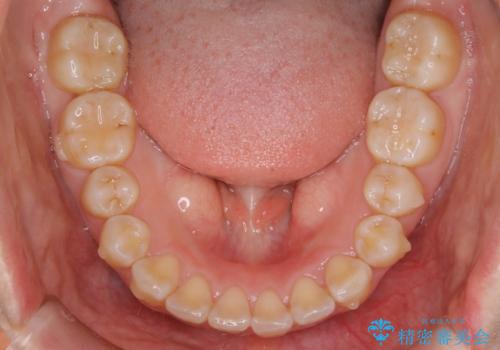

【非抜歯】ガタつきと歯軸を正して長持ちする歯へ

- 歯のガタつきと噛み合わせの改善を主訴に来院されました。

非抜歯で、少量の奥歯の移動と歯列の拡大・IPRを駆使して主訴を改善するための治療計画を立案しました。